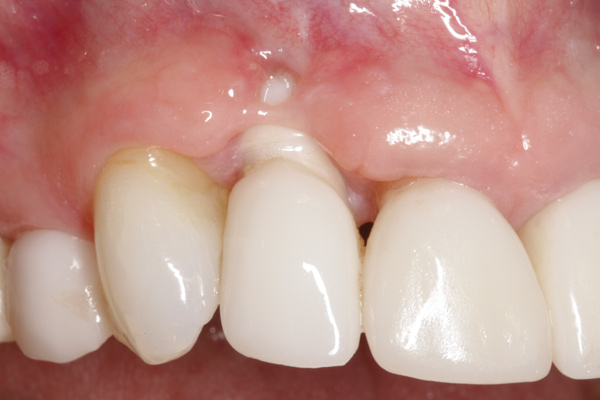

Fig 3. Initial buccal view of tooth No. 7.

Figure 3

To predict peri-implant esthetic outcomes, Kois described five essential diagnostic keys that need to be assessed before removing a periodontally hopeless tooth (Figure 3 and Figure 4): (1) relative tooth position; (2) form of the periodontium; (3) periodontal biotype; (4) tooth shape; and (5) position of the osseous crest. Failing teeth that have a thick, flat gingival biotype, are square shaped, and have < 3 mm vertical distance from the position of the facial and interproximal crest have the lowest risk of developing recessions after implant placement.23 Therefore, implant surgery may be performed by either an open flap or flapless approach. However, teeth with a thin soft-tissue biotype, a highly scalloped gingival architecture, and a triangular shape that are positioned facially have less-predictable peri-implant esthetic outcomes. When a tooth presents with these unfavorable anatomical features, grafting procedures should be considered both before and after tooth extraction to prevent vertical loss and facial collapse of the gingival architecture.21 Flapless tooth extraction should be attempted in the esthetic zone to maintain blood supply from the periosteum and endosteum and maximize healing potential (Figure 5).44 In addition, several surgical protocols have been proposed to avoid peri-implant mucosal recessions, including 3-dimensional implant positioning,45,46 the use of platform-switching implants,47,48 and soft-tissue augmentation.8,49,50